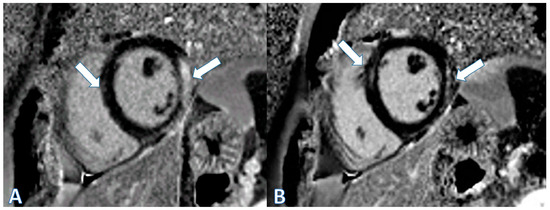

| CMR at hospitalization | LGE of both pericardial leaves and foci of late subepicardial enhancement on the basal inferolateral, lateral, and inferior walls | LGE at the level of the pericardial leaves and a basal inferolateral subepicardial focus | Edema and LGE in the lower-middle, inferolateral, and anterolateral segments | Edema and LGE at the anterolateral, basal-mid inferolateral and basal inferior segments, and intramyocardial in the mid-inferoseptal and apex segments |

| Control CMR at 6–9 months | Persistence of LGE on the inferolateral wall | - | LGE in the inferolateral and anterolateral walls | LGE intramyocardial and subepicardial at inferolateral, anterolateral, and inferoseptal walls (reduced extent) |

| Control CMR at 2 years | - | - | LGE in the inferolateral and anterolateral walls (reduced extent) | - |